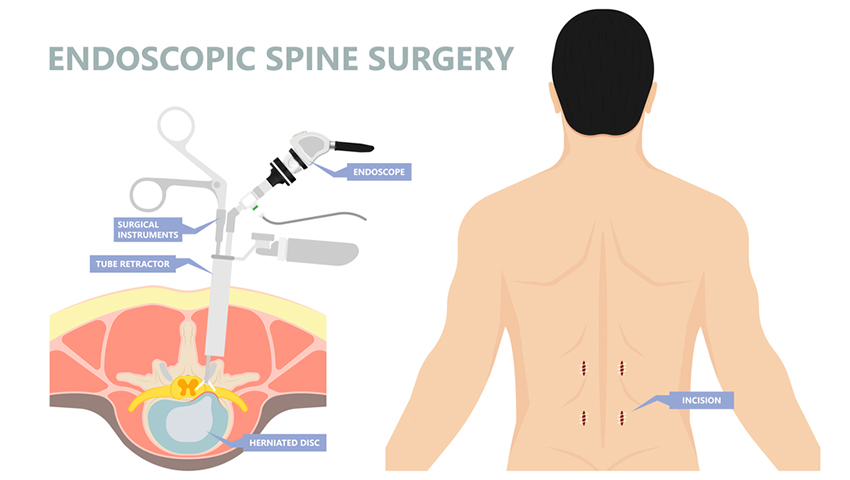

Comparing Endoscopic Spine Surgery to Traditional Open Surgery: Which Is Right for You?

Recovery After Endoscopic Spine Surgery: What to Expect and How to Prepare

Understanding Endoscopic Spine Surgery: A Minimally Invasive Solution for Back Pain